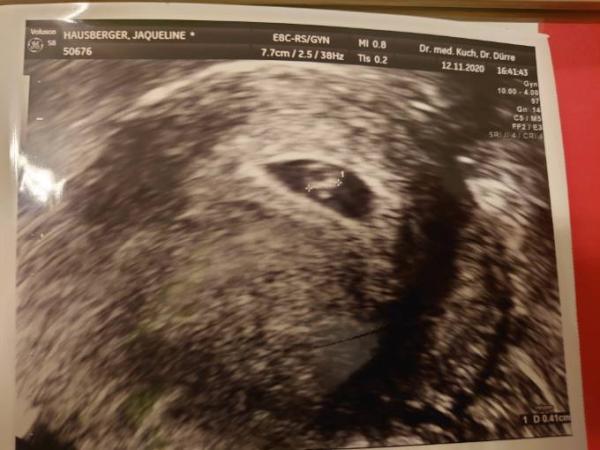

Das wird schon Das ist mein erstes Bild gewesen aber es war auch schon was Wert.

Bild zu